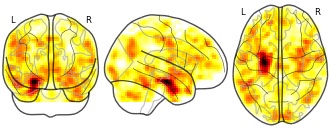

High Functioning Autism Functional Connectivity R-scored Maps: sAHA

License information was derived automaticallyDescriptionsmoothed r-scored maps TempPole_Left

Collection description

22 adolescents and young adults with ASD from the local community and from the University of Campinas. A trained and qualified clinician made the diagnosis of ASD using the DSM-5 criteria after interviewing the family and examining each patient. A second investigator confirmed the diagnosis using the “Current” Scores of the Autism Diagnostic Interview-Revised (ADI-R). The ADI-R is a clinical diagnostic instrument for assessing autism in children and adults. The ADI-R provides a diagnostic algorithm for autism as described in both the ICD-10 and DSM-IV and is one of the most important validated ASD measures available in Brazil. Child testing and parent interviews should be viewed as complimentary and necessary components of the diagnostic evaluation after the clinical evaluation and DSM-5 criteria. All patients were required to have a full-scale IQ greater than 85, as measured by the Wechsler Abbreviated Scale of Intelligence.

Exclusion criteria comprised a history of major psychiatric disorders (e.g. depression, psychosis), seizure, head injury, toxic exposure and the evidence of genetic, metabolic or infectious disorders. We also excluded individuals with secondary autism related to a specific etiology such as tuberous sclerosis or Fragile X syndrome. Thirteen individuals in the ASD group were using a variety of psychoactive medications. Nine subjects were not under psychoactive drug treatment. Five subjects were taking psychostimulants, seven were taking antipsychotics and six were taking selective serotonin reuptake inhibitors (SSRIs). Six of these subjects were using more than one of the medications listed above. Participants were instructed not take any medication one day before their visit.We are including FC maps derived from 5 distinct seeds: PCC (the MNI coordinate −41 13 −29); medial frontal region (MNI 0 49 −3); left amygdala (MNI −23 −4 −20); left anterior hippocampus (MNI −24 −13 −20); left temporal pole (−41 13 −29)

Modality

fMRI-BOLD